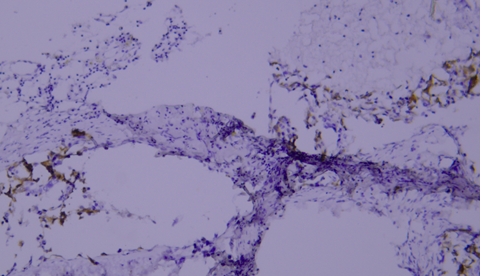

典型实例:人扁桃体石蜡组织切片Lysozyme染色,因边缘效应出现非特异性染色(黑色箭头区域)。

解决建议:确保组织切片与玻片黏贴牢固,试剂完全覆盖组织以防止干片;使用加入Tween-20的缓冲液,可减少边缘效应的发生。